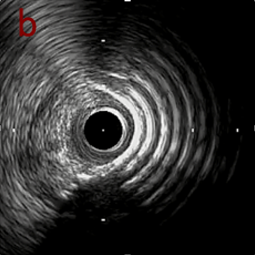

IVUS imaging

IVUSでは8時方向からPD枝がはいいてくる。

PreのIVUSではaの部位のみlipid plaqueを認め削ることでdistal embolismのリスクがあり、そのほかは270度の偏心性石灰化であるがwire biasは良好。